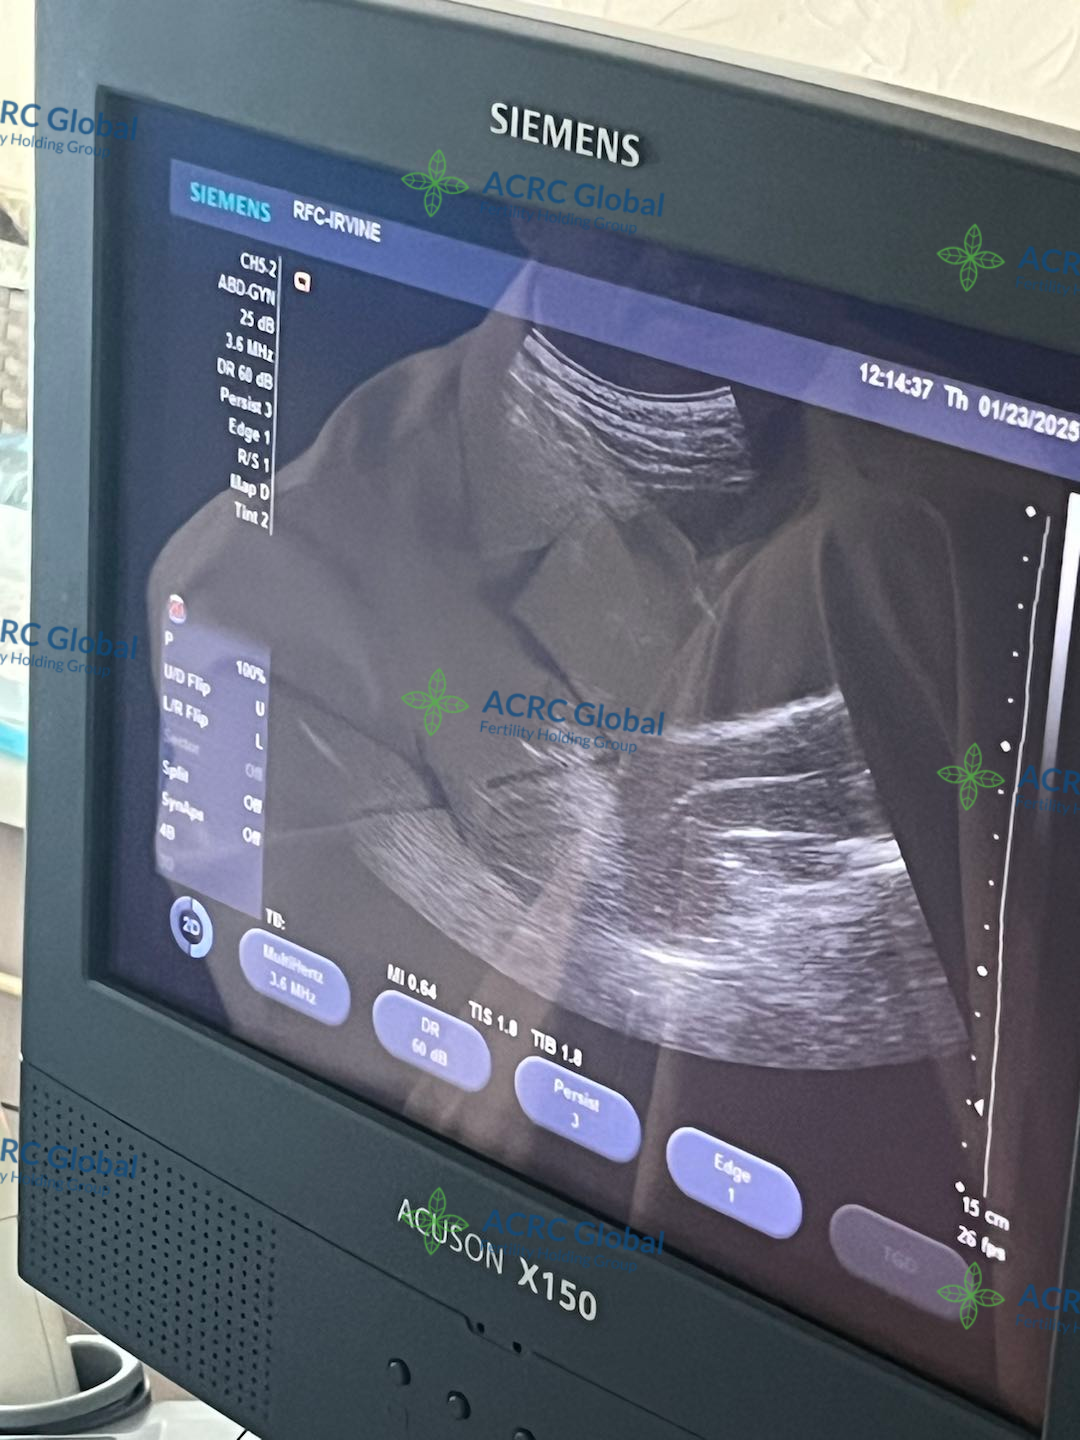

爱妈V的双胎移植也迎来了B超检查,两个宝宝都顺利着床了,宝宝A看起来非常活泼,一直在动,宝宝B则显得格外冷静,两个宝贝性格差异已经初见端倪,实在太有趣了!两位准爸爸听到这个好消息激动不已,已经约定好下一次产检时一同到场,为爱妈加油打气,给予满满支持!

爱妈D的首次胎心监测来了!宝宝现在才7周零两天,虽然小得像一颗蓝莓,但这个小小的生命已经跳动出了有力的心跳声💓小小的你是全家的希望,满怀信心地期待着你从诊所“毕业”!